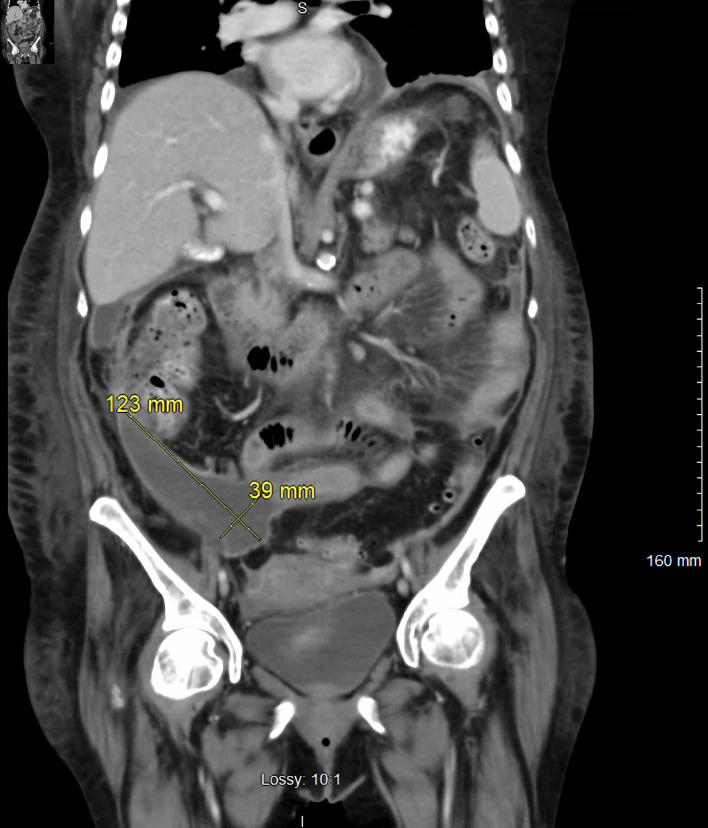

Abstract Image